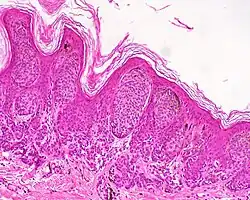

| Junctional nevus | Along the junction of the epidermis and the underlying dermis.[15] | May be colored and slightly raised.[16] |

|

ICD10: D22 ICDO: M8740/0 |